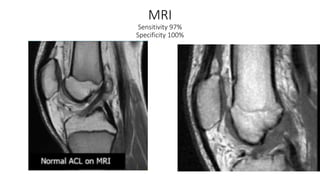

MRI

Sensitivity 97%

Specificity 100%